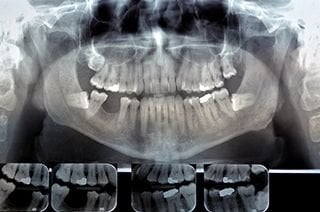

Digital X-Rays

Digital X-rays are obtained by putting a small electronic sensor in the mouth, and captured images can be pulled up instantly on a computer screen.

Digital X-ray images are clearer than traditional X-rays and your healthcare provider can zoom in and out, making it easier for them to detect potential problems.